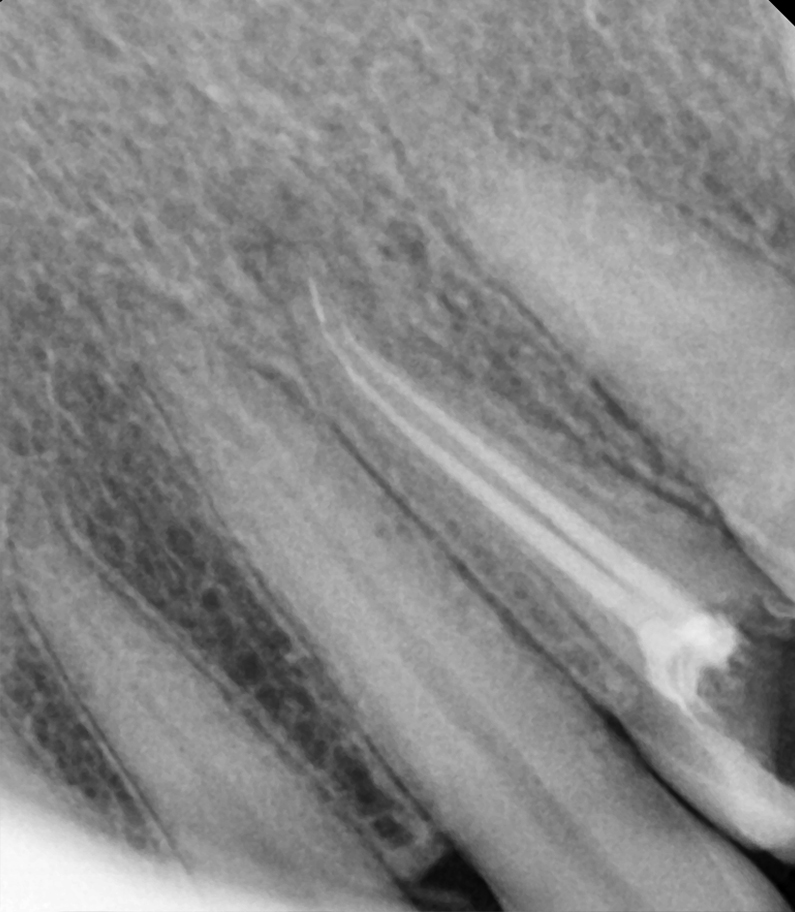

Severe pain and discomfort is going to be one of the problems of not treating the tooth. Without treatment the blood vessels and nerves inside the tooth become severely infected and that’s when pus and abscesses form. An abscess is swelling full of pus usually located at the end of the root canal because of the buildup of the infection. The abscess can be so serious that it causes swelling around the face, eye or the neck.

Stages of tooth decay

• Decay in pulp painful

• Tooth abscessunbearable pain